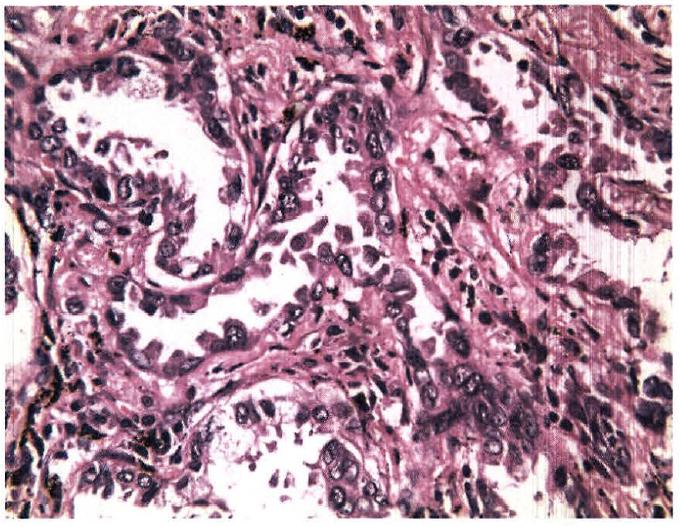

三、从病理上看小细胞肺癌的“坏” 作为肿瘤诊断的金标准,是何如区分小细胞肺癌与非小细胞肺癌的。一般而言,对于预后比较好的肿瘤,大多都能有一定的形态,长得比较像样;但对于那些比较坏的,预后差的肿瘤,很多是不像样堆积,细胞形态上也长得比较奇怪。

肺腺癌:癌细胞沿肺泡壁呈多层生长,形似腺样结构,有乳头形成,肺泡间隔未被破坏,肺泡轮廓保留